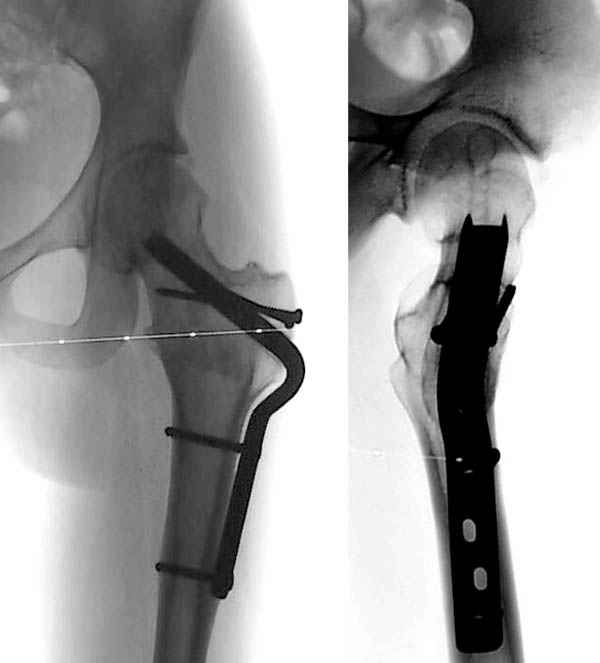

Если стабильность юношеского эпифизиолиза доказана, тогда можно провести коррегирующие операции. Все открытые методы репозиции опасны высоким процентом осложнений из-за повреждения кровоснабжения головки.

На основе этой работы был предложен анатомичекий доступ к проксимальному отделу бедра, так называемый Digastric или Flip Trochanteric Approach.

Доступ удобен при "circumcision osteoplasty" при импинжменте, при переломах головки, лабральной патологии, при удалении медиальных остеофитов из дна вертлужной впадины, а также при коррекции проксимальной части бедра.

Характерным отличием является то, что Vastus Lateralis and Gluteus Medius остаются прикрепленным к кости. Остеотомия трохантера на уровне прикрепления мышц, потом капсулотомию делают в форме Z вместо Т, что дает лучший обзор. При вывихе головки артерия циркумфлекс защищается сухожилием обтуратора интернус.

Здесь представлен один из случаев остеотомии на шейке после остаточного явления юношеского эпифизиолиза из Flip Trochanteric доступа.